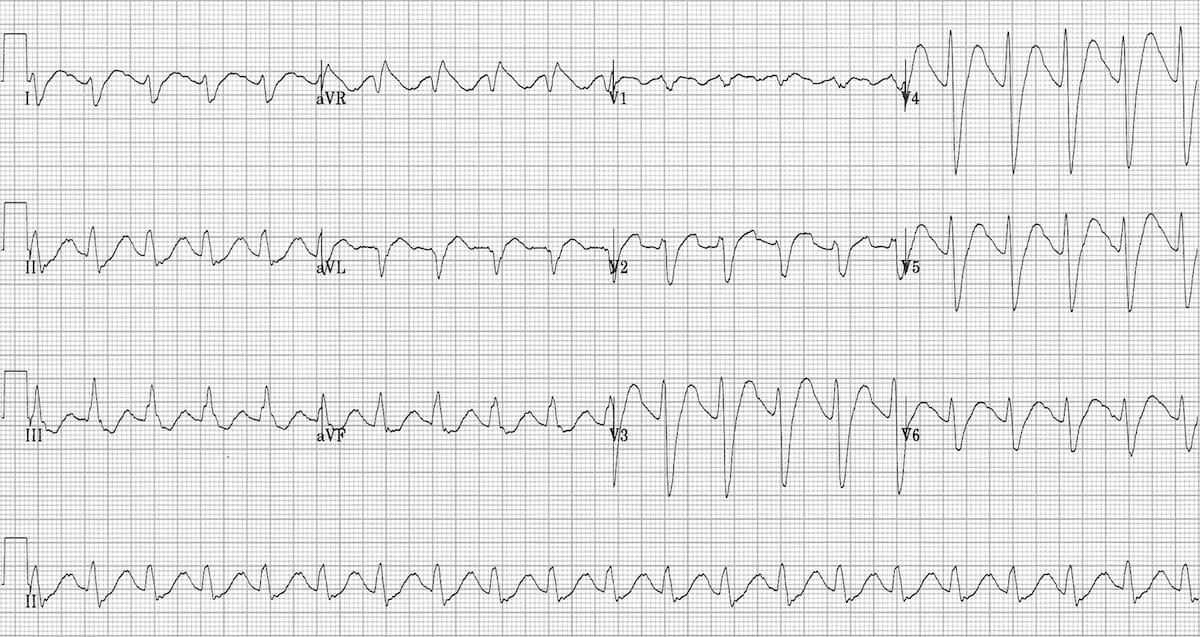

This is an ECG of monomorphic VT. Note the very regular, broad complex tachycardia and the same QRS morphology throughout.

https://litfl.com/ventricular-tachycardia-ecg-library/

© Life in the Fast Lane. Licensed under CC BY-NC 4.0

This is an ECG of polymorphic VT (specifically, Torsades de Pointes – a type of polymorphic VT). The varying QRS morphology can be appreciated, with the characteristic morphology of QRS complexes “twisting” around the isoelectric line.

https://litfl.com/torsades-de-pointes-ecg-library/

© Life in the Fast Lane. Licensed under CC BY-NC 4.0